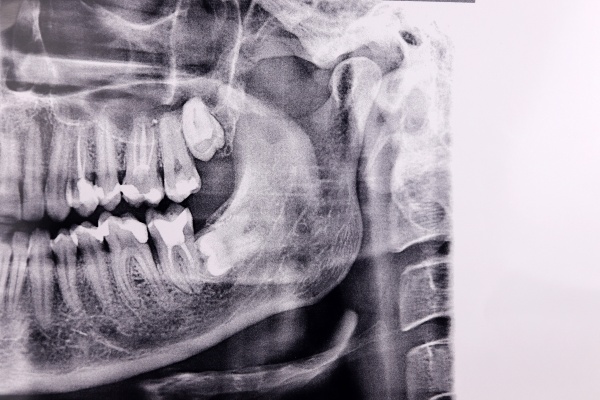

CBCT-cone beam 3D imaging is a modern diagnostic technology. This imaging device is used when traditional dental x-rays cannot adequately capture the images necessary to plan a patient's treatment. The cone beam imaging system reconstructs three-dimensional images of a patient's oral cavity, including the teeth, jawbone, soft tissues, nerve pathways, and beyond.

The 3D cone beam imaging scan is a prompt, minimally invasive experience. The CBCT device involves a cone-shaped X-ray beam that takes up to 600 images while rotating around the patient's head. This 10-40-second process captures multiple angles of the oral structure, directly transferring them to our computer software to produce 3D images.